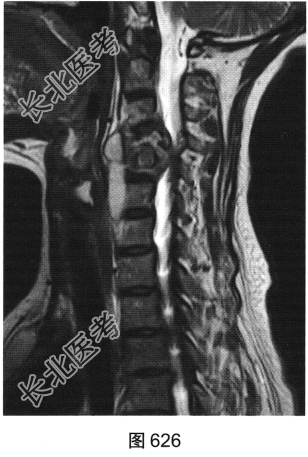

- [材料题] 患者男性,34岁,近数月乏力,偶有低热。颈部疼痛2个月余,逐渐加重,有轻压痛,颈部活动受限。

- 多项选择题2.[提示]患者行颈椎X线、CT和MRI检查,见图623~图628。首先应考虑患者为下列哪种疾病( )